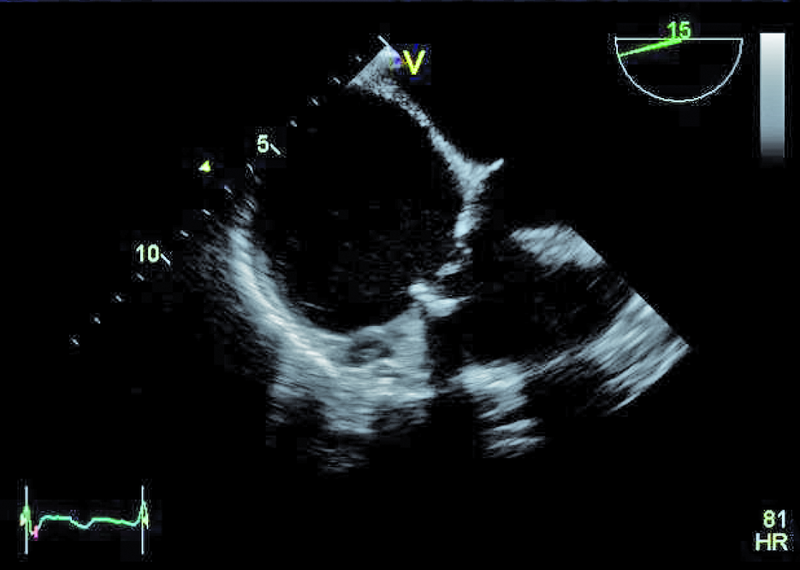

Szczegóły oceny układu krążenia z okresu przeprowadzanych operacji nie były znane. Można było jedynie przypuszczać, że śluzak prawej komory mógł zaburzać funkcję zastawki trójdzielnej, a jego resekcja pozostawiła stopniowo narastającą nieszczelność zastawki. Wymiana zastawki na biologiczną była konieczna, ale spowodowała dalsze problemy u chorego. Degeneracja zastawek biologicznych u osoby młodej może postępować dynamicznie, nawet bez obecności dodatkowych czynników nasilających to zjawisko, jak niewydolność nerek czy nadczynność przytarczyc. Kolejnym czynnikiem, poza wiekiem, wpływającym na odpowiedź immunologiczną, może być samo ujście trójdzielne, w którym procesy wapniowo-fosforanowe w odpowiedzi na rozciąganie płatków są silne. Warto także nadmienić, że zastawki biologiczne stentowe, jak użyta w tym wypadku, charakteryzują się szybszym tempem zwyrodnienia niż zastawki bezstentowe. Rozpoznanie strukturalnego zwyrodnienia bioprotezy w ujściu trójdzielnym nie powinno nastręczać trudności. Wczesnymi objawami procesu jest pogrubienie i usztywnienie płatków, które stają się w obrazie ultradźwiękowym jaśniejsze i nieregularne w zarysie (ryc. 1, 2). Ponieważ proces postępuje, włóknienie i zwapnienia obejmują najpierw spoidła, a następnie całe płatki i pierścień zastawki. W przedstawionym przypadku zwyrodnienie prowadzi zarówno do stenozy, jak i niedomykalności. O stenozie zastawki w ujściu trójdzielnym zawsze należy myśleć, gdy gradient średni napływu przekracza 6 mm Hg (ryc. 3). Niedomykalność trójdzielna uważana jest za istotną, kiedy talia strumienia ma szerokość co najmniej 6 mm (ryc. 4). Warto dodać, że rejestrowane zmiany hemodynamicznie są podobne do tych, jakie obserwuje się w natywnej zastawce trójdzielnej np. w rzadkim uszkodzeniu poreumatycznym. Chory ma wskazania do kolejnej interwencji kardiochirurgicznej i operacja w tym wypadku nie powinna być odkładana, żeby nie doprowadzić do narastającej niewydolności jam prawego serca. By uzupełnić ocenę, zarejestrowano projekcję na drogę odpływu prawej komory (ryc. 5). Wykluczono cechy nadciśnienia płucnego i niedomykalność zastawki płucnej. Zwrócono uwagę na istotnie poszerzone jamę prawego przedsionka i żyłę główną dolną (ryc. 6), odpowiadające nieprawidłowościom w badaniu fizykalnym – hepatomegalii i obrzękom obwodowym. Poza operacją można rozważyć wykonanie zabiegu techniką przezcewnikową i wszczepienie zastawki Edwards SAPIEN lub Melody (valve-in-valve). W tym wypadku na decyzji o leczeniu operacyjnym zaważyły jednak preferencja chorego i doświadczenie ośrodka.